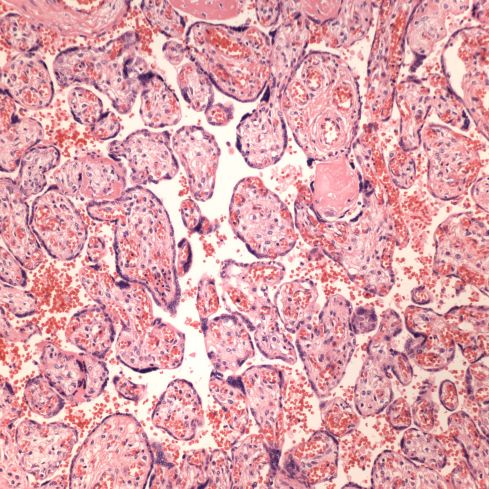

Gradual heart failure fails to explain the neuronal necrosis present in the basis pontis, Sommer sector of the hippocampus, putamen, and lateral geniculate nucleus (Fig 3,4). Based on experimental studies, the neuronal necrosis is the result of an acute asphyxial event followed by at least hours of survival. The meconium aspiration in this infant can be a marker of acute asphyxia (Fig 5,6). Some areas of villi demonstrated red cell fragmentation in the villous stroma, but most areas did not show this change (Fig 7,8). No thrombi were seen in the three samples taken. The evidence indirectly supports a diagnosis of fetal thrombotic vasculopathy, but is not definitive. Fetal thrombotic vascuopathy has been proposed as an important marker of compromised umbilical cord blood flow. One explanation of the relationship is based on cord compromise fulfilling Virchow’s triad for thrombus formation including blood stasis and hypoxic endothelial injury (similar to sitting too long or being in a cast).

Figure 7 placental villi: These normal appearing villi composed the majority of the villi that were not infarcted.

Figure 8 placental villi: This large foci of villi demonstrates a smudged appearance of the villous stroma with extravasated, sheared red cells. This lesion occurs with downstream occlusion of fetal blood flow.